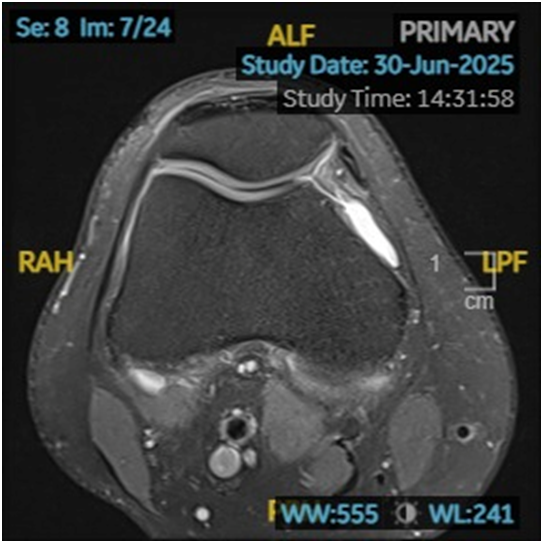

Hình 1. Ròng rọc xương đùi bình thường

Loạn sản ròng rọc xương đùi (Trochlear Dysplasia) là một dị tật bẩm sinh hiếm gặp của khớp gối, đặc trưng bởi sự phát triển bất thường của rãnh ròng rọc, tức là phần lõm ở xương đùi nơi xương bánh chè trượt lên xuống khi gập hoặc duỗi gối.

Ở người bình thường, rãnh ròng rọc có hình chữ V, sâu và đối xứng, giúp định hướng và giữ xương bánh chè trượt đúng hướng khi gập duỗi khớp gối. Tuy nhiên, khi bị loạn sản:

- Rãnh trở nên quá nông hoặc thậm chí phẳng

- Gây mất ổn định cho xương bánh chè

- Dễ dẫn đến trật khớp bánh chè tái phát, đau, và thoái hóa khớp sớm

Ở khớp gối, ròng rọc xương đùi đóng vai trò là “đường ray”, còn xương bánh chè là “bánh xe” di chuyển. Khi đường ray bị biến dạng (quá nông hoặc lệch trục), “bánh xe” sẽ dễ trượt khỏi đường, gây ra hiện tượng trật khớp bánh chè.